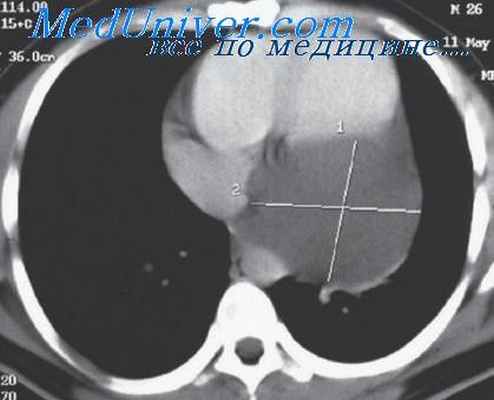

Рентгенологические симптомы перикардиальных целомических кист довольно характерны. Локализация тени относится чаще к плевроперикардиальному правому углу (у 5 из 6 наших больных). Форма тени обычно овальная, по интенсивности недостаточно плотная, сливающаяся в некоторых позициях с тенью перикарда. Контуры тени хорошо очерчены, часто пульсируют.

В прямой проекции вырисовывается только верхненаружный контур тени, а нижний — сливается с тенью сердца и диафрагмы.

- Рентгенологическую диагностику: рентгеноскопию и рентгенографию грудной клетки, рентгеноскопию сердца с контрастированием пищевода. Рентгенологически целомическая киста перикарда определяется как шаровидная или овальная тень, обычно локализующаяся в кардиодиафрагмальном синусе. Наружный контур тени четкий, внутренний обычно сливается с тенью сердца, а нижний – с тенью диафрагмы. Характерно наличие передаточной пульсации. Раньше для диагностики целомических кист перикарда широко использовалась пневмомедиастинография, однако на современном этапе ее успешно заменила КТ грудной клетки.